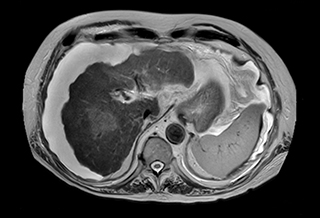

Ascites can be hard to image, but excellent result is obtained with Ingenia Ambition. This high resolution image demonstrates the high quality that can be obtained with VitalEye and the patient just breathing normally. The acquisition time is fast thanks to the accuracy of the respiratory gating with VitalEye** and it also saves the time needed to put a respiratory belt on the patient.

3D T2 with VitalEye